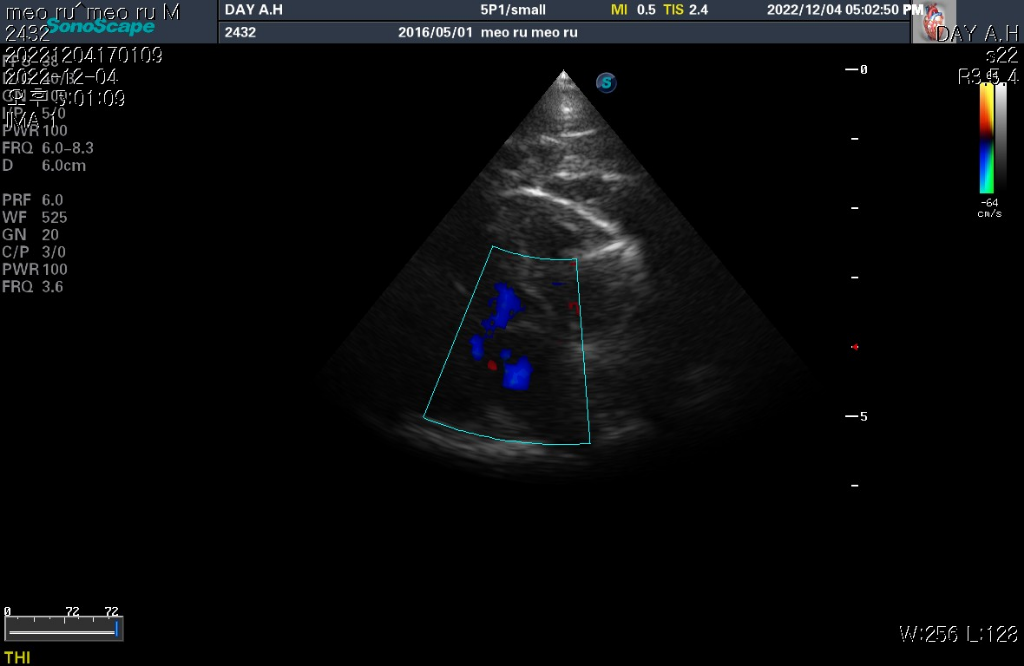

하지만 심장 질환의 잠정적 확진 golden standard는 심장 초음파 검사로 심장 초음파 검사상 심장의 벽 구조가 6mm이상이라면 HCM의 가능성이 매우 높다고 판단합니다.

현재 첨부한 사진상에서 6mm이상의 직경을 보이는 사진들이 존재하기 때문에 해당 검사를 진행한 수의사의 기준상 HCM의 가능성이 높다고 판단하는것은 합리적입니다.